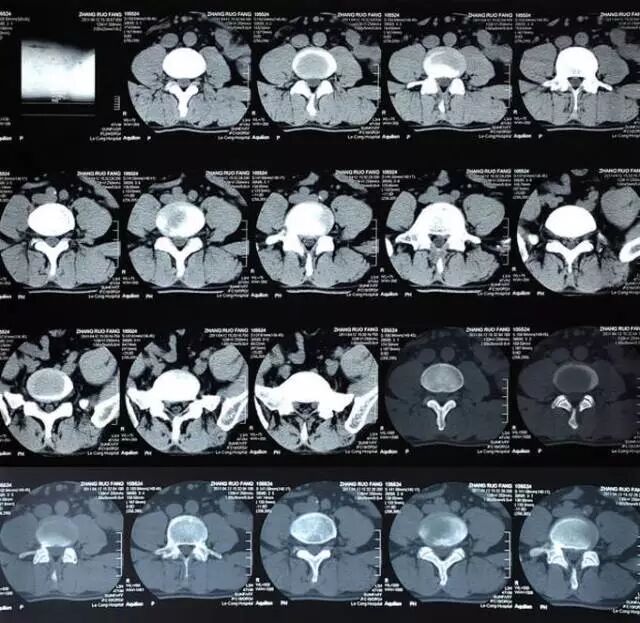

CT也是用射线穿透身体,但跟X线检查不同,现在多排螺旋CT检查是通过采集扫描范围内人体的每一个体素进行成像,说白了就是把要检查的部位划分无数体积不足一个立方毫米的微小方块,看得更细,很细微的病变也能被发现。

CT最常用在头部、胸部、腹部和脊柱疾病等方面的检查,有些四肢和骨骼问题用X线检查看不清楚时,也可以选择做CT。目前体检项目中的CT主要是胸部CT,用于早期肺癌筛查。